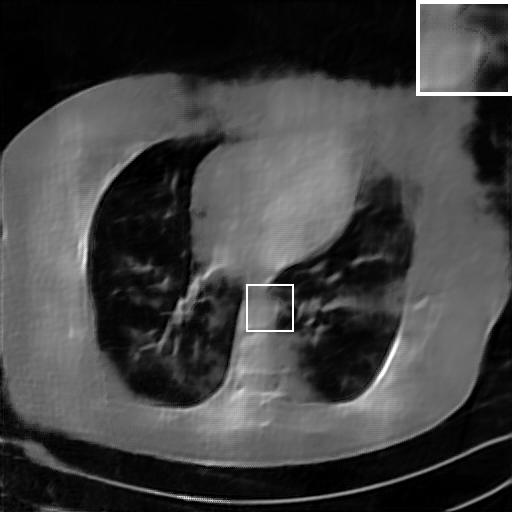

Due to the statistical error of low photon counts, Poisson noises are introduced and result in random thin bright and dark streaks that appear preferentially along the direction of the greatest attenuation [41]. Table V lists the PSNR, RMSE, and SSIM of different methods on raw data scanned within a limited scanning angle and corrupted by Poisson noises, where Poisson noises correspond to 100 incident photons per pixel before attenuation. Unlike white Gaussian noises, the performance of the TV model is significantly better than the post-processing learning method FBP-Unet. And all other learning-based methods work better than the TV model in terms of PSNR, RMSE and SSIM. Our LRIP-nets still provide the best reconstruction accuracy among all the learning-based methods for the scanning angle of , , and , respectively. It demonstrates that the LRIP-nets are also effective for data contaminated by Poisson noises.

Fig. 7 manifests the reconstruction results of these methods with scanning angular of . It can be seen that both FBP and FBP-Unet produce serious artifacts within the range of missing angles. The TV model performs well in removing Poisson noises, but it can not handle the artifacts very well. Similarly, there left obvious artifacts on boundaries and different degrees of missing in visceral tissues of the reconstruction images obtained by the SIPID, PD-net and FSR-net. The visceral tissue and boundaries of our LRIP-net reconstructions are more intact and smoother, especially for the LRIP-net1/8 which gives the ideal boundaries. The observation becomes even apparent if we look at the zoom-in regions, where the LRIP-nets can produce results with fine structures. Therefore, we conclude that the low-resolution image prior can effectively improve the qualities of the limited-angle CT reconstruction.